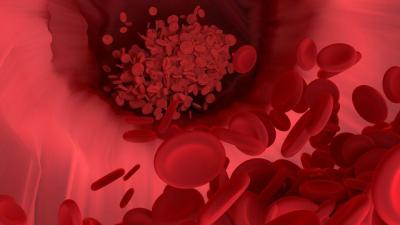

यात रिसर्चकर्त्यांनी असा दावा केला आहे की कोरोना व्हायरस शरीरातील रक्तवाहिन्यांना आणि रक्ताच्या पेशींना पूर्णपणे खराब करून अवयवांवर परिणाम करत असतो. फुप्फुसांनंतर रक्तवाहिन्यावर कोरोना व्हायरस अटॅक करतो.

त्यानंतर शरीरातील वेगवेगळ्या अवयवांपर्यंत होणारा रक्तपुरवठा सुरळीत होत नाही. रक्तपुरवठा संथ गतीने होतो. परिणामी किडनी, आतड्यांची समस्या अधिकच वाढत जाते.

आरोग्यतज्ञ रुचित्जका यांनी सांगितले की मी आत्तापर्यंत अशा तीन केसेस पाहिल्या आहेत. ज्यात कोरोना रुग्णांच्या रक्तवाहिन्या या व्हायरसने संपूर्ण भरलेल्या होत्या. त्यामुळे शरीरातील अवयवांवर नकारात्मक परिणाम दिसून येत होता.